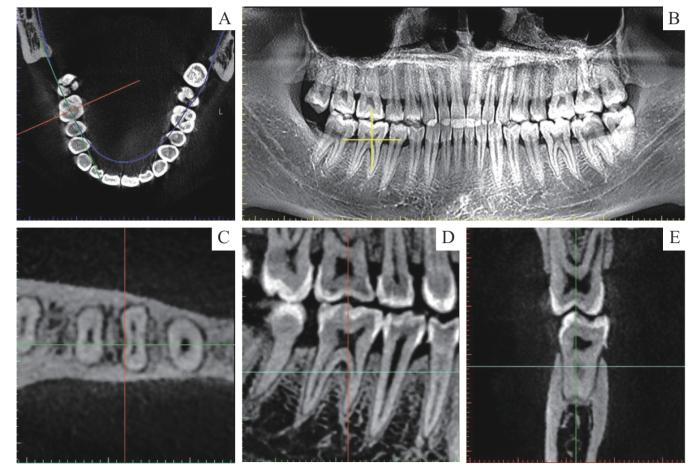

SmartV图像分析软件的观测界面包括全景水平面、全景界面、局部水平面、局部冠状面和局部矢状面(图1)。在全景界面上将“+”标记定位到下颌第一磨牙;在局部水平面,从髓室底至根尖区层面滚轴连续移动观察,区分三根管型和四根管型。通过调整,使得水平面标线与待测根管的长轴垂直,冠状面和矢状面的标线通过待测根管的长轴。

图1

SmartV图像分析软件观测界面

Note: A. A panoramic view of the horizontal interface. B. Panoramic interface. C. Partial horizontal interface. D. Partial coronal interface. E. Partial sagittal interface.

Fig 1

Observation interface of SmartV image analysis software